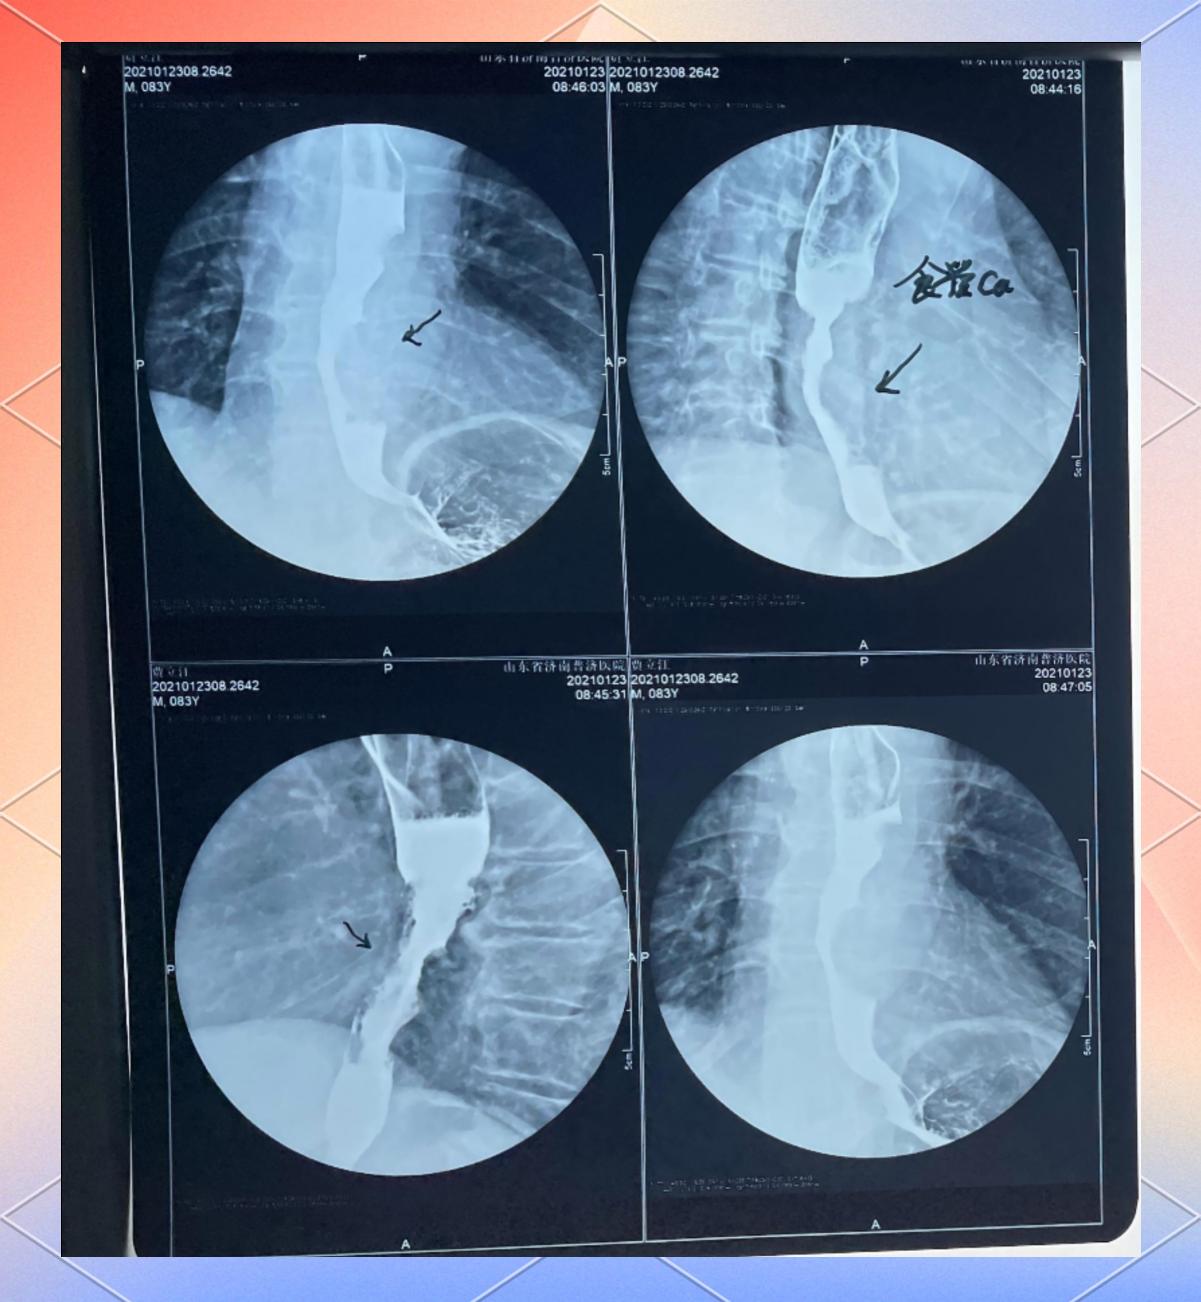

12、4 胃癌胃癌是胃壁增厚的严重病因,由癌细胞浸润性生长导致胃壁僵硬增厚早期症状隐匿,可能仅表现为消化不良进展期可出现上腹疼痛食欲减退体重下降及黑便胃镜及病理活检是确诊关键,CT或PETCT可评估肿瘤分期及转移情况总结胃增厚并非独立疾病,而是多种病理过程的共同表现其病因涵盖良性。